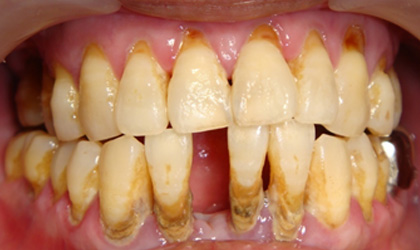

牙周病不處理會怎樣 ?

嚴重時,因為牙齒沒有牙周支撐,將導致牙齒鬆動、脫落。

如果沒有治療,牙齒喪失的數目經常不單只是一顆牙,往往是多顆牙齒,甚至於全口牙拔掉。

牙周病有什麼症狀 :

1. 刷牙時或不自覺的牙齦出血

2. 牙齦顏色由粉紅色變為暗紅色

3. 牙齦紅腫、疼痛甚至化膿

4. 牙齒酸軟無力;對冷熱食物敏感

5. 牙齦萎縮,齒牙慢慢移位,齒間出現間隙

6. 牙齒鬆動

7. 口臭